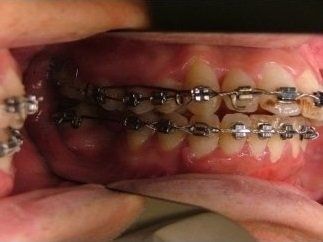

Il trattamento ortodontico non è solo per i bambini: se hai denti storti, affollati, mancanti o prominenti che ti impediscono di masticare e parlare liberamente, potrebbe essere necessario rivolgersi a uno specialista. L’ortodonzia prevede l'uso di apparecchi ortodontici, che possono essere fissi o rimovibili.

I dentisti studiano infatti le anomalie di costituzione, posizione e sviluppo di denti e ossa mascellari, e progettano l’apparecchio mirando al ripristino della corretta funzionalità dell'apparato masticatorio.

- può migliorare l'aspetto e la funzione dei denti;

- la capacità di parlare e masticare può essere migliorata;

- denti più dritti facilitano lo spazzolamento e per questo sono meno soggetti a carie e altre patologie.